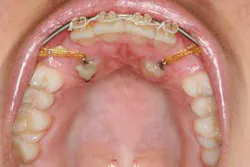

When a full permanent dentition is present (with the exception of impacted canines), the labial/palatal position of the canine will have an influence on what the provider can do. (1) Arguably, obtaining a CBCT is considered mandatory and will allow for a more inclusive treatment plan creation. If angulation is favorable, then consideration to remove the primary canine and wait six months to see if there is movement of the permanent canine is an option. If extraction of the canine(s) is needed, then a premolar substitution, which is dependent on occlusion, can be used in the space. An implant can also be an appropriate alternative. When pulling a canine into the occlusal arch, there is risk involved. Trauma to adjacent teeth (root resorption) and ankylosis are some of the most common complications.The patient was put in full orthodontics and referred to a surgeon for extraction of the primary canines, exposure, and placement of retention on the impacted canines to pull them directly down from their current position.

A ballista appliance was used to prevent a facial pull of the canines in order to avoid and prevent resorption of the roots of the lateral incisors. As movement progressed over the course of the next year, eruption of the canines was considered a success. Once in position, they will be pulled facially into occlusion.

The patient is pleased with the progress reached thus far and is ecstatic at the anticipation of a successful outcome.